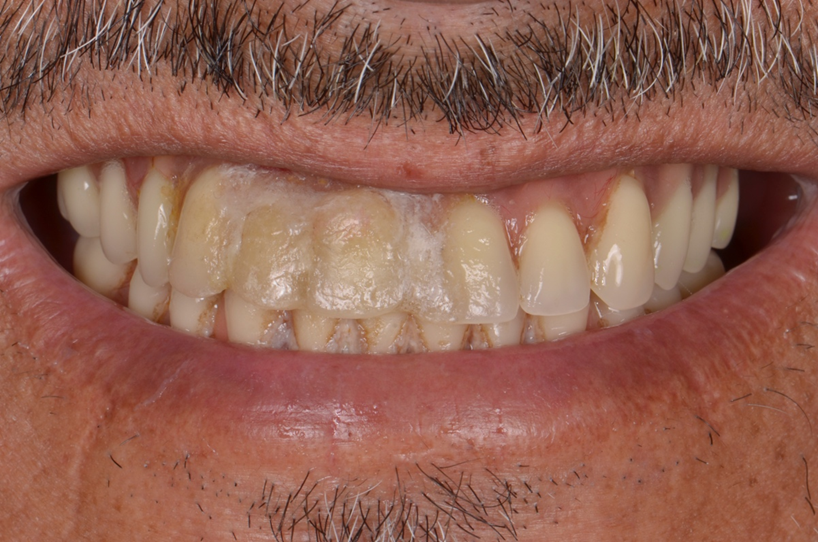

Um homem de 65 anos apresentou-se para consulta a fim de realizar uma nova prótese total superior fixa implantossuportada, pois a sua prótese já se apresentava muito antiga e bastante inadequada, tanto esteticamente, quanto funcionalmente. O exame clínico abrangente revelou que os implantes do arco superior se apresentavam saudáveis e em um bom posicionamento tridimensional, e a relação esquelética de Classe III de Angle exibia uma exposição gengival mandibular ao sorrir (Figura 2). Após a apresentação e discussão das diversas opções de tratamento, o paciente optou por prosseguir com a reabilitação total dos implantes superiores com uma nova prótese total fixa implantossuportada em zircônia.